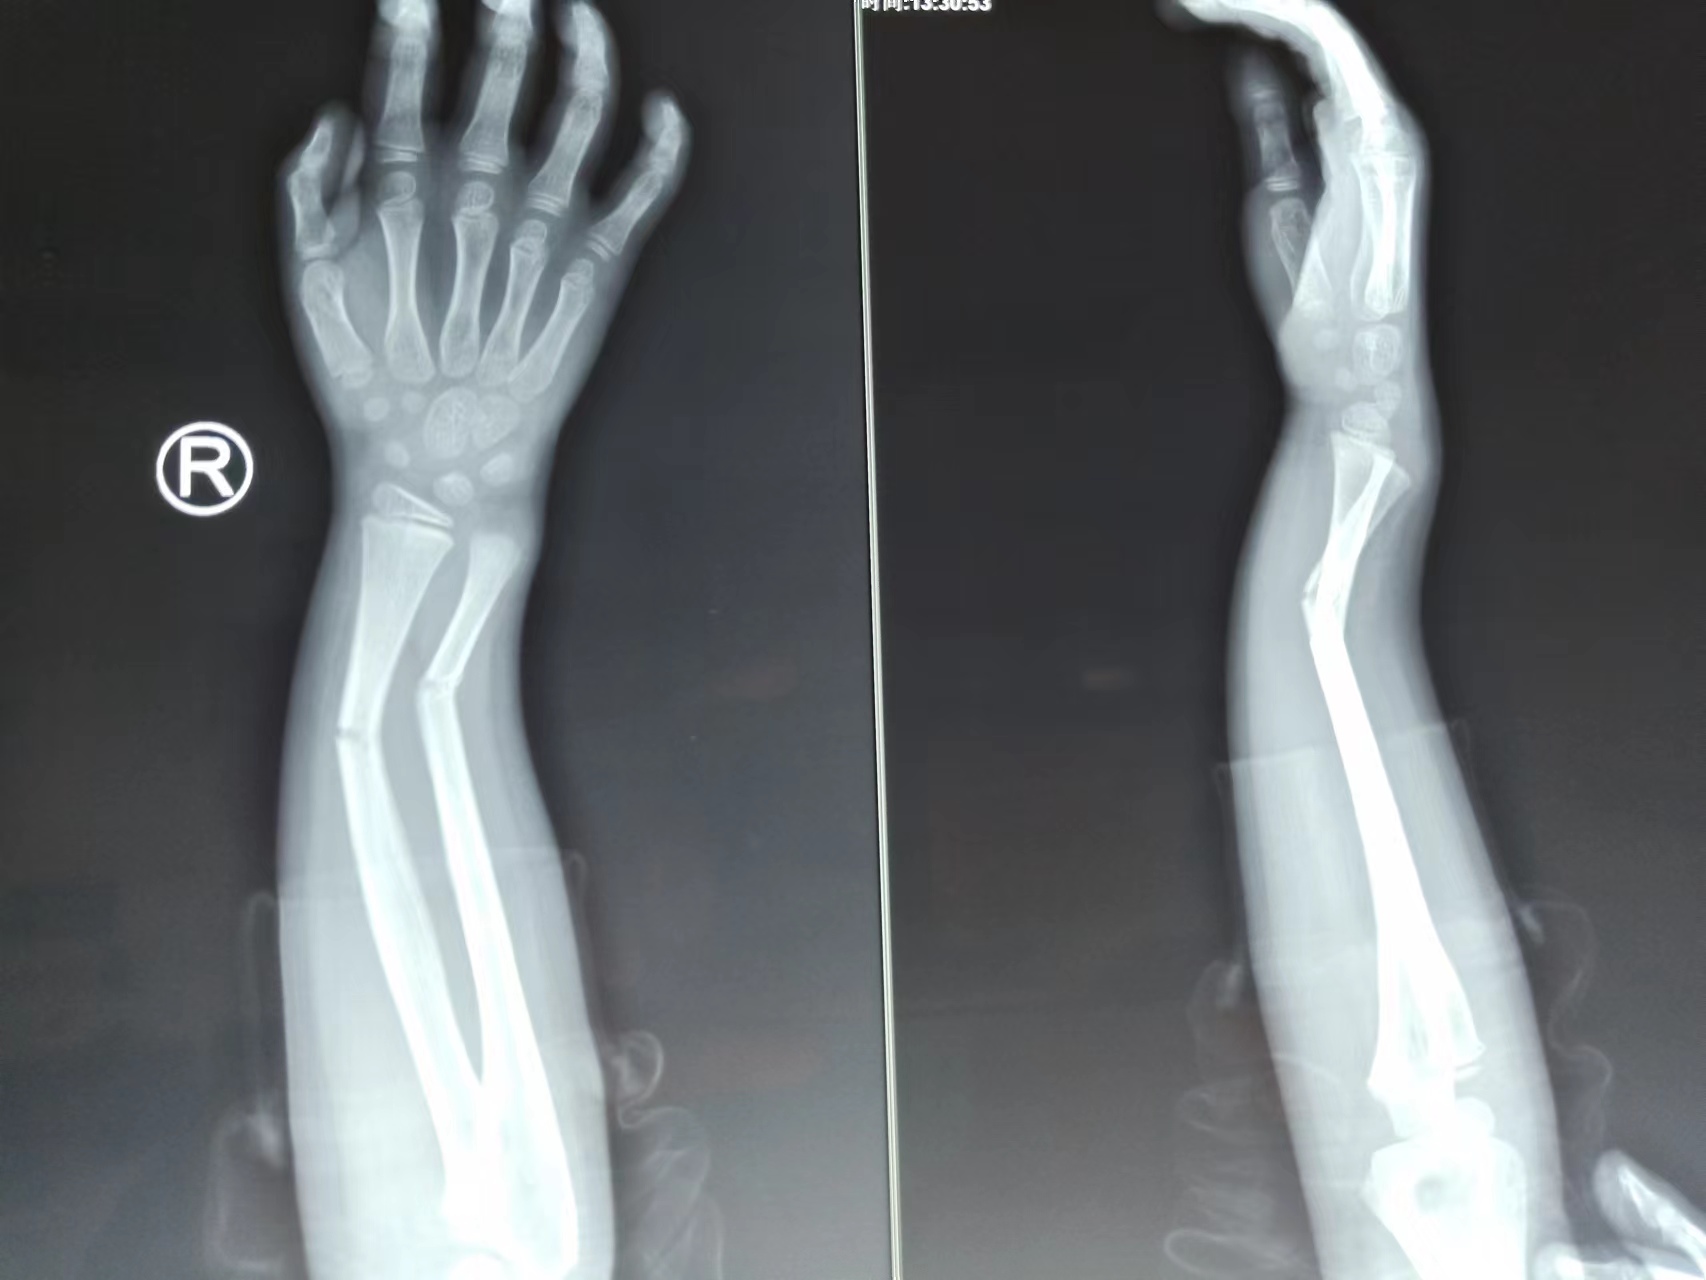

“东昌府区中医院骨伤二科医生的接骨技术太神奇了,简直找不到骨折线了”。2022年4月30日早上,五一小长假第一天,骨伤二科李学锋主任刚到办公室,患者家属许先生将一面写着“医者父母心,仁德值千金”的锦旗送到了医生办公室,以此表达对骨伤二科精湛的医术和暖心服务的感谢。 ![]() 据了解,许先生的儿子今年6岁,在幼儿园玩耍时摔伤右侧前臂,在当地医院建议穿针治疗,许先生恐惧手术,经多方打听,了解到东昌府区中医院骨伤科的治疗理念是能简单的不复杂,能手法整复的不切开手术。来到骨伤二科住院后,医生仔细研判该患儿的受伤机理和X线片,最终采用手法整复,三垫加压,夹板固定。整复完拍摄X线片示骨折端解剖复位。 ![]() 整复前 ![]() 整复后 金杯银杯不如老百姓的口碑,一面锦旗,传递的不仅是患者的感激之情,也是东昌府区中医院骨二科医护人员对病患服务的最好证明。东昌府区中医院骨伤二科将一直秉持“把患者利益放在第一位”的原则,尽职尽责为患者服务,并坚持用专业的技术和人性化的关怀,不断提升患者就医体验感。